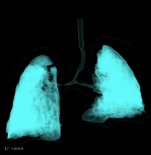

胸部CT增强图像如下:

左肺动脉起源异常,由右肺动脉发出,在气管隆突上方与食管之间形成不完整的环状结构。双肺散在分布多发实变影。

左肺动脉吊带,伴双肺感染